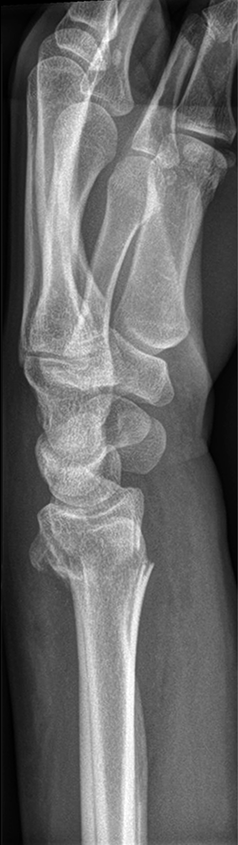

The patient was a 25-year-old woman who sustained a displaced, unstable extraarticular fracture of the left distal radius while snowboarding.

After closed reduction a dorsal re-dislocation of 25° occurred (Fig 3a). There are additional apparent signs of instability: dorsal comminution (Fig 3a) and fracture of the ulnar styloid (Fig 3b). Therefore, a considerable potential for further dislocation is present which is likely to occur in a cast. This young, active, and demanding patient wishes to return to her activities as early as possible. This can only be achieved with an operative fracture fixation. The nail was chosen instead of a plate. This allowed an almost instant functional use of her hand, which allowed her to return to work at 2 weeks postoperatively without additional fixation or a splint and full unprotected function of her wrist at 6 weeks.